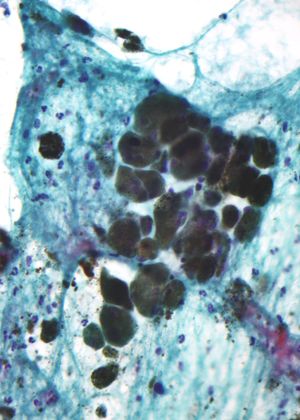

الميلانين Melanin []ˈmɛlənɪn[] (باليونانية: μέλας - melas، "أسود، داكن"، هو مصطلح واسع يطلق على مجموعة من الصبغات الطبيعية الموجودة في معظم العضيات (العنكبوتيات هي واحدة من المجموعات القليلة التي لا تحتوي على الميلانين). يُنتج الميلانين عن طريق أكسدة الحمض الأميني التيروسين ثم بلمرته. تُنتج الصبغة ضمن مجموعة خاصة من الخلايا تُعرف بالميلانوسيت.

هناك ثلاثة أنواع رئيسية من الميلانين: الإيوميلانين، الفيوميلانين، والنيروميلانين. أكثر أنواع الميلانين شيوعاً هو الإيوميلانين. يوجد نوعان من الإيوميلانين - الإيوميلانين البني والإيوميلانين الأسود. الفيوميلانين عبارة سيتين - يحتوي على وحدات پوليمر البنزوثيازين الأحمر المسئولة بشكل كبير عن لون الشعر الأحمر، وصبغات أخرى. النيروميلانين يوجد في المخ، على الرغم من أن وظيفته لا تزال غامضة.

الظهور المجهري